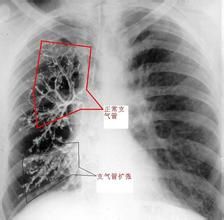

支氣管肺發育不全(bronchopulmonarydysplasia,BPD)是由多種因素造成的一種慢性肺損害,因多發生在未成熟兒及患肺透明膜病套用高濃度氧和機械通氣存活後,並且其主要病理改變為肺纖維化,故又稱為呼吸機肺或纖維增生性慢性肺病,現也稱作慢性肺疾病(chroniclungdisease,CLD),有學者將BPD、Wilson-Mikity綜合徵和慢性未成熟兒肺功能不全

為早產嬰透明膜病後或遷延不愈或好轉後又出現呼吸窘迫及缺氧,面色蒼白,出汗,嗜睡,嘔吐,乾咳,氣促,發紺,呼吸困難,輕度肋間隙凹陷,肺部有濕囉音和哮鳴音,有呼吸暫停發作,需吸氧和輔助通氣,病程遷延數周至數月,出現進行性呼吸衰竭和心力衰竭,常有右心衰的表現,如肝大,末梢水腫,頸靜脈怒張等,動脈血氣分析可發現有低氧血症和(或)高碳酸血症,臨床上可見患兒生長遲緩或停滯,恢復者於1~2歲內常有反覆下呼吸道感染,依賴氧和呼吸器生存。